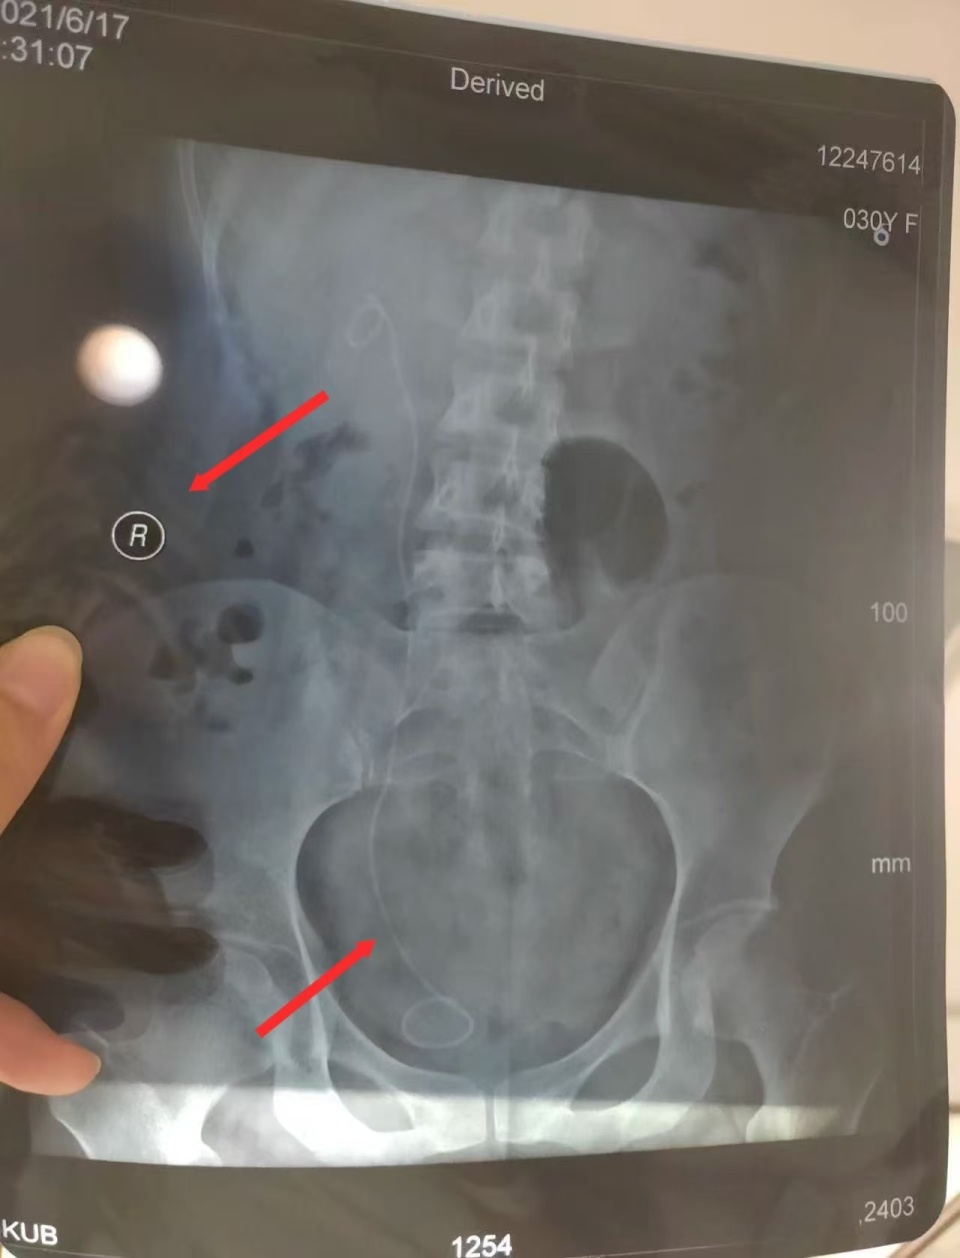

“医生为我确定了左输尿管手术方案,包括术前谈话以及手术知情同意书上,主刀医生也都是这位医生。2021年4月21日下午手术顺利进行,不久后出院。”朱女士说,直到术后两个月,她到医院复查拍CT后才发现,自己原本健康的右输尿管内被施行了手术,患病的左输尿管反而没有手术。朱女士提供的手术知情同意书显示,病情诊断为左侧肾盂积水伴输尿管狭窄等,拟定手术为左侧输尿管镜检备扩张/内切开。而在手术记录中,诊断仍为左侧肾盂积水伴输尿管狭窄等,但手术名称却成了右侧输尿管扩张术,右侧输尿管镜检查术。

为了明确责任,朱女士向上海市静安区卫健委申请医疗事故鉴定,静安区卫健委移交上海市医学会组织鉴定。鉴定报告认定,华山医院虽然诊断正确,但手术方案有误,存在告知缺陷。2021年4月19日,医方手术知情同意书拟定手术为“左侧输尿管镜狭窄伴左肾积水”,4月21日,术中医方自行变更手术方案且依据不足(患者既往各项检查如超声、CTU、MR均提示泌尿系病变在左侧,术后超声检查亦显示病变在左侧),术中未向患方进行告知并取得患方知情同意,术后亦未告知患方该情况,患方至6月17日门诊复查时知晓该情况。医方告知存在缺陷,在一定程度上延误了患者左侧输尿管病变第二次治疗,时间约2个月。上海市医学会认为,朱女士与华山医院医疗争议构成医疗事故。根据相关规定和条例,认定本病例属于四级医疗事故,医方承担完全责任。